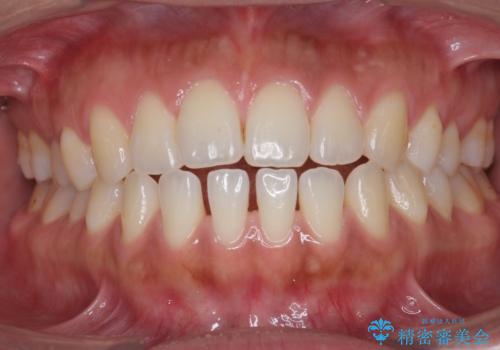

受け口、すきっ歯を インビザラインで モニター治療

- 前歯のすき間と受け口を気にして来院。

マウスピースでしっかり閉じています。